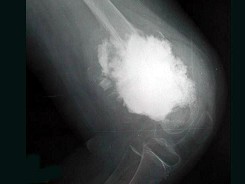

女,10岁,左大腿疼痛,夜间加重,肿胀明显,结合图像,最可能的诊断是()

• C.骨肉瘤